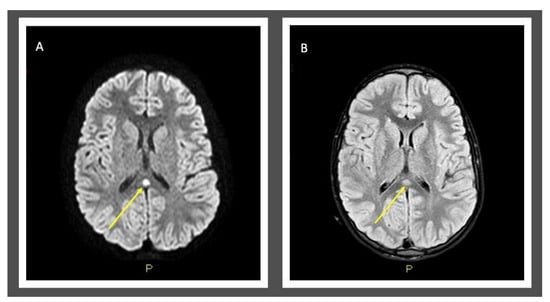

| 1 | MERS is rare clinic-radiological syndrome characterized by acute mild encephalopathy and brain MRI lesion evident in the splenium of corpus callosum (type I) that could extend into callosal radiations, frontoparietal subcortical white matter, to the rest of corpus callosum, and cerebellum (type II). |

| 4 | Consider MERS in children with clinical signs of encephalopathy (neurologic symptoms or alterations of the state of consciousness) during a viral infectious event and investigate it with brain MRI exam and DWI examinations. |